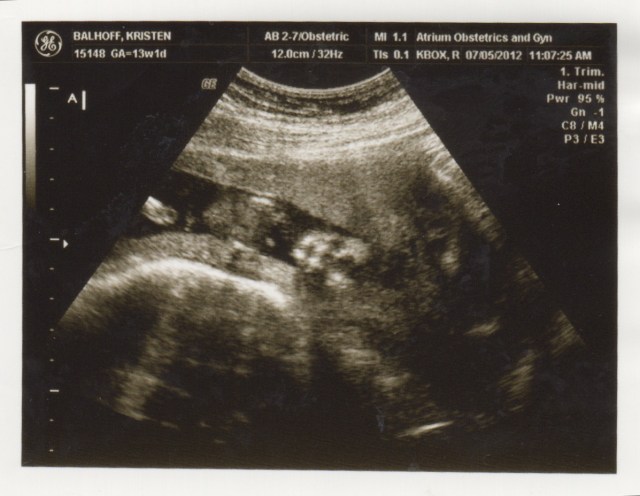

Here’s Baby B – crown to rump, head to the right, facing down, at 13 weeks:

Baby B – crown to rump, head to the right, at 13 weeks